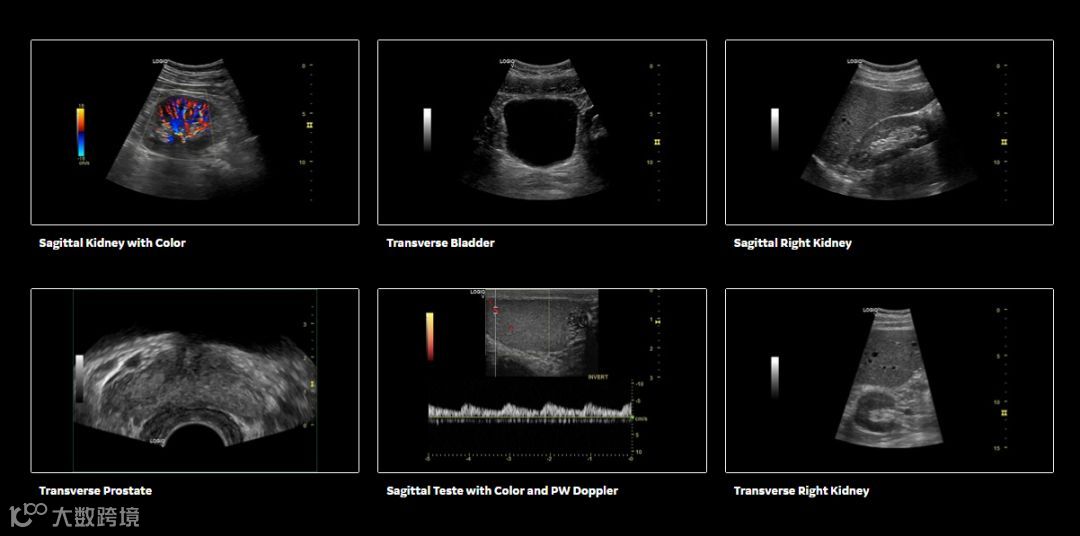

GE超声目前三大产品线Logiq系列,Voluson系列,Vivid系列,型号齐全,产品丰富。尤其以妇产的Voluson系列产品最为经典,从Voluson 730开始,到E8,再到目前的E10。但凡新的产品推出,都能在全球掀起一阵GE妇产旋风,受欢迎程度可见一斑。